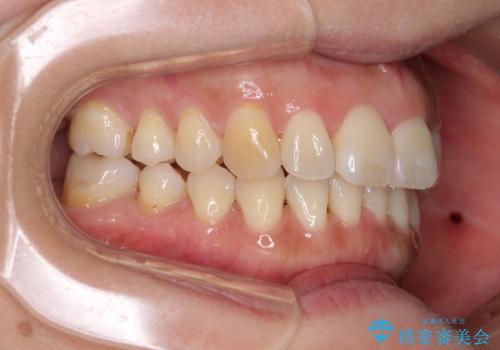

インビザライン・ライトは、製作できるアライナーの枚数に制限があるため、移動可能な量に限りがあります。

一方で、半年から1年程度で治療を終えることができるため、軽度の歯列不正の患者様には大変お勧めです。